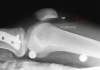

- Small

This patient presented with a history of dislocated right patella.

There is a small amount of fluid in the supra- patella pouch (left arrow) and in Hoffa's Triangle (right arrow).